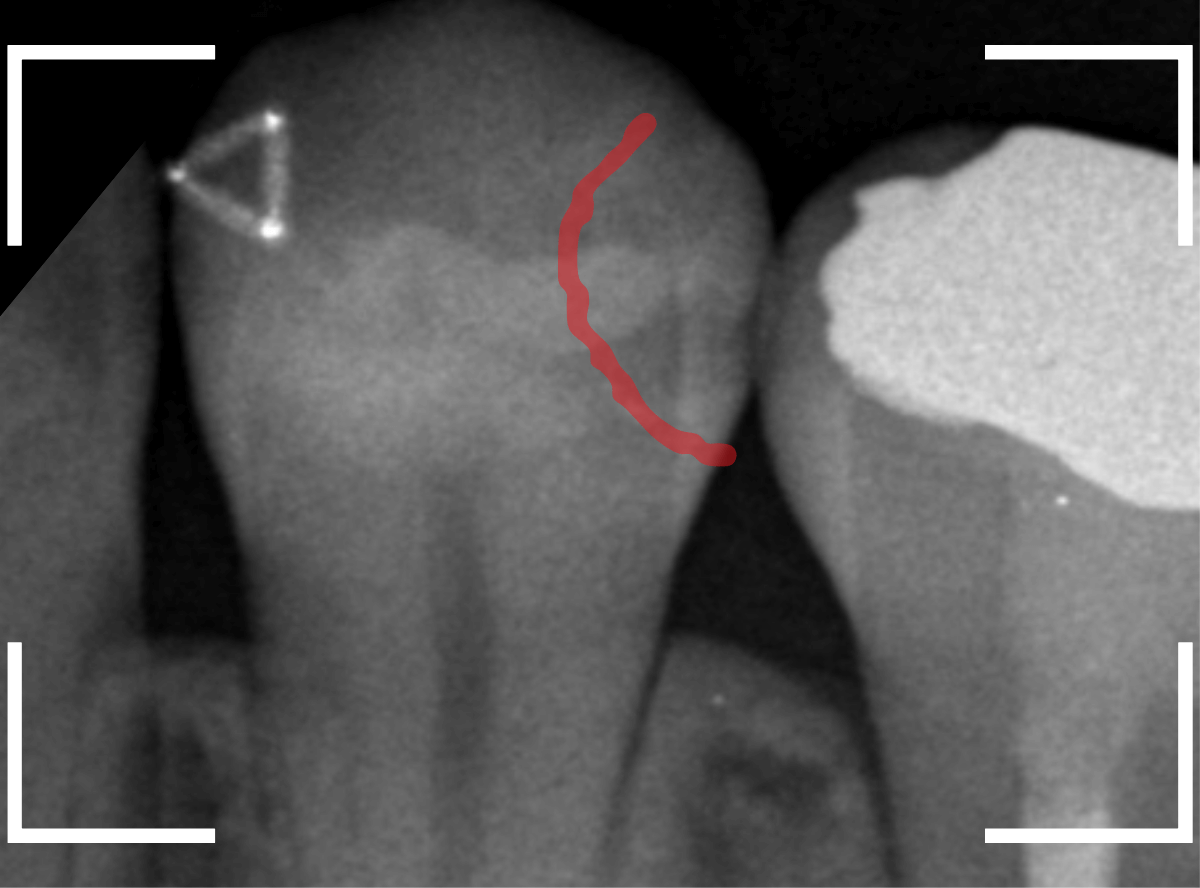

Case.22 痛みはないけど、歯のすきまから大きな虫歯

上の小臼歯の間が虫歯になっていた患者さんです。

症状はありませんし、見た目からも虫歯があるかはわかりませんでした。

レントゲン写真で確認します。

赤い線が虫歯、青い線が歯の神経です。

歯のすきまから両側に虫歯が大きく広がっているのが確認できます。

治療を開始します。

少し削ると、中からすぐに虫歯が出てきました。

ある程度、虫歯を除去したところで、う蝕検知液で確認します。

赤く染まっている部分が虫歯です。

まだまだ虫歯が中で残っている状況で、かなり深い虫歯なのが確認できます。

全ての虫歯を除去しました。

レントゲン写真からある程度確認出来ましたが、歯の神経スレスレまで虫歯が進行していました。

ここまで虫歯が進行していても、全く症状を感じない事も多いです。

そして、ある時急に痛みを感じるのです。

虫歯は急に進行しません。

治療後の定期検診で確実に食い止めましょう。